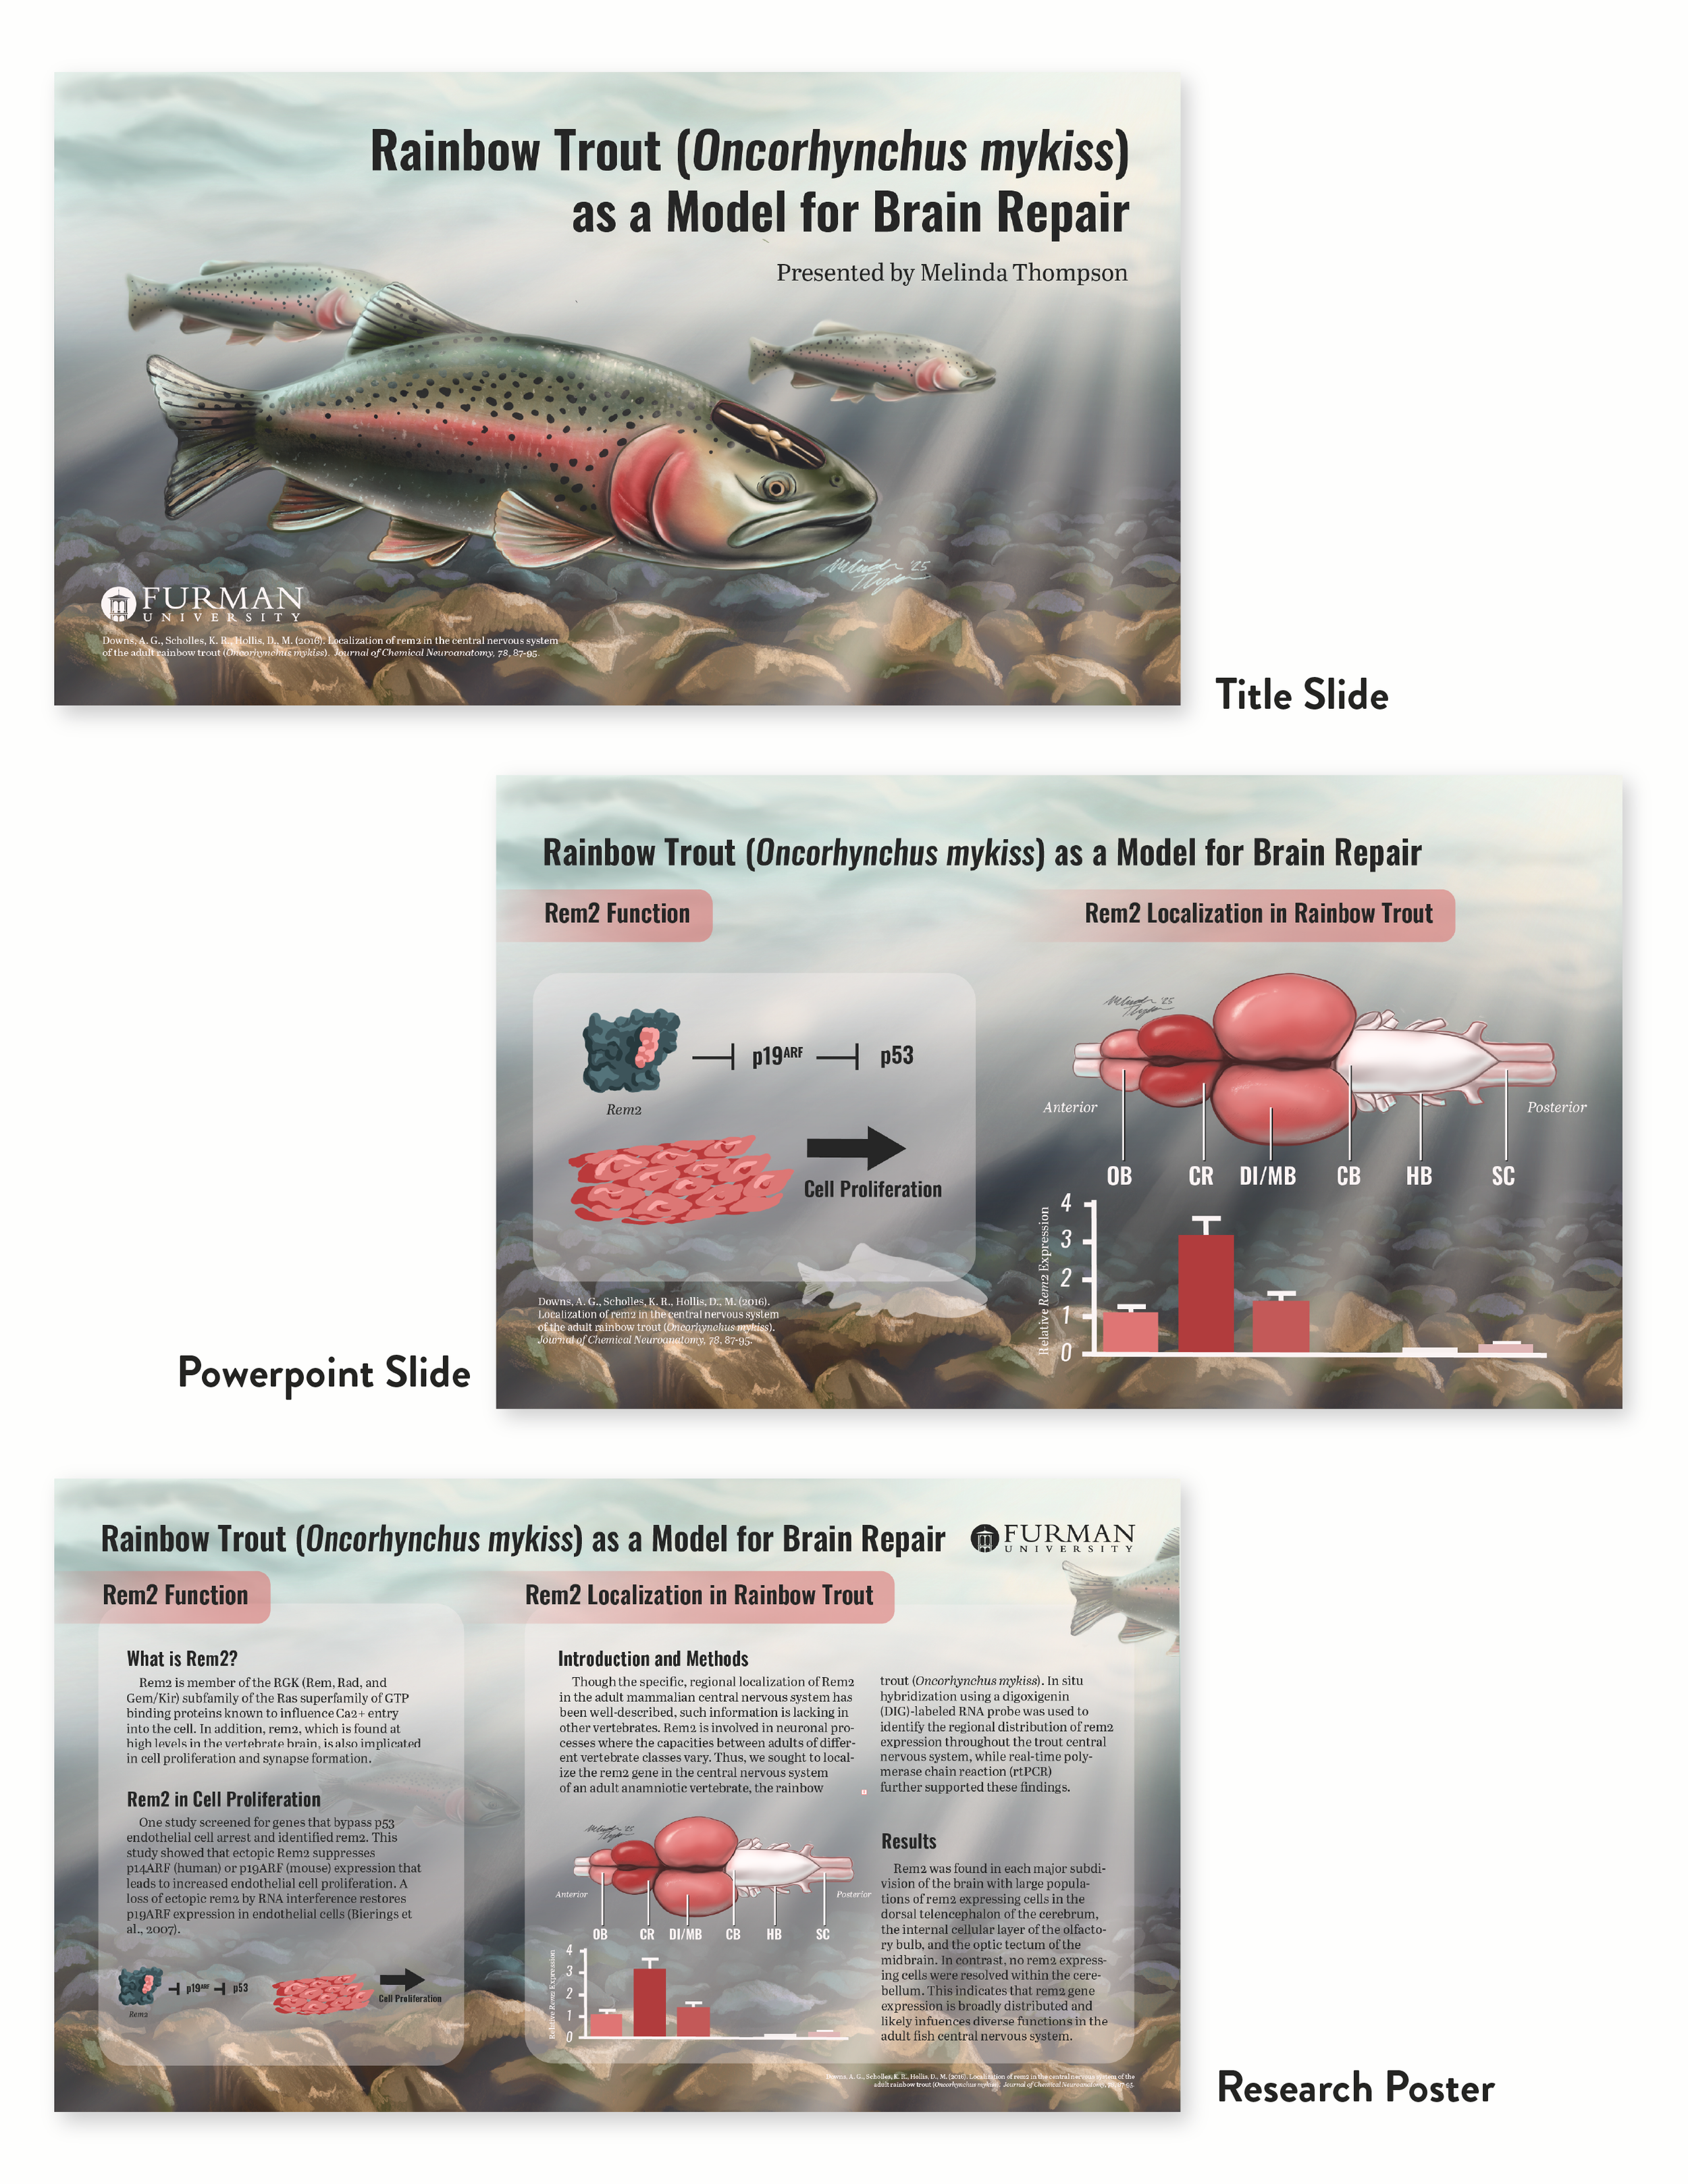

Research Conference Slides: Rainbow Trout as a Model for Brain Repair